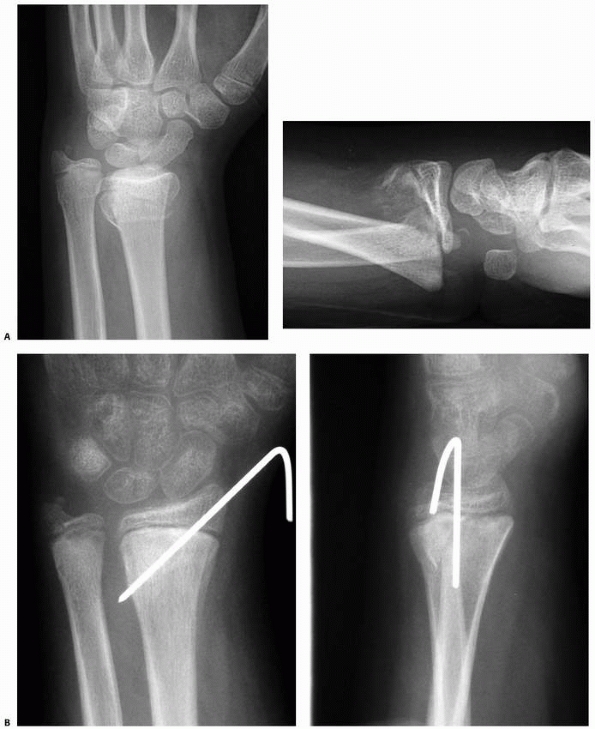

![]() |

|

FIGURE 9-19 A. AP and lateral views of a displaced Salter-Harris type II distal radial fracture. B. AP and lateral views 1 month after simple pin fixation.

FIGURE 9-20 A. A markedly displaced Salter-Harris type IV fracture of the distal radius in an 11-year-old boy who fell from a horse. B. Radiograph taken 3 weeks after closed reduction demonstrates displacement of the comminuted fragments. C.

Eighteen months after injury, there was 15 mm of radial shortening, and the patient had a pronounced radial deviation deformity of the wrist. |